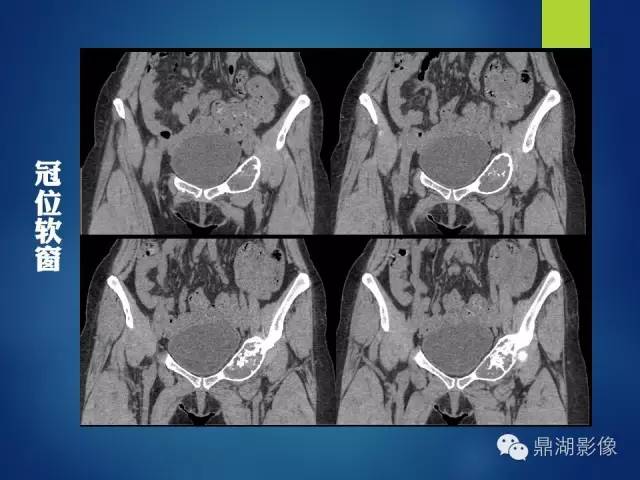

影像表现:

左侧耻骨可见一不规则略低于软组织密度影,周围骨皮质变薄,其内可见丝瓜囊样密度增高影,未见明显骨膜反应及骨折线。

X 线表现为侵蚀骨质破坏,可见软组织肿块。CT 能更清楚地显示其钙化,但不广泛。肿块含水量多,故在CT像上表现为低密度;黏液型软骨肉瘤较普通型软骨肉瘤更常见出血,在MRI的T1WI、T2WI 上均表现为高信号, (肿块) 增强扫描肿块呈轻度强化。

影像学上的表现基本反映了病理学的特点:

(1) 溶骨性改变,X 线、CT 表现为低密度,MRI 上,T1WI为低信号,T2WI 为高信号;

(2) 出现“环形弧样”钙化;

(3) 浸润性特征,骨内膜呈扇形增厚并常见软组织肿块,增强肿块为边缘强化或分隔样强化。